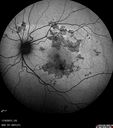

INDOCYANINE GREEN ANGIOGRAPHY: The indocyanine green angiogram, which was shot out to fifteen minutes shows dense geographic blocking of the indocyanine green in the geographic areas. There are many more spots visible on indocyanine green angiogram than there are either on funduscopic or on fluorescein angiogram.